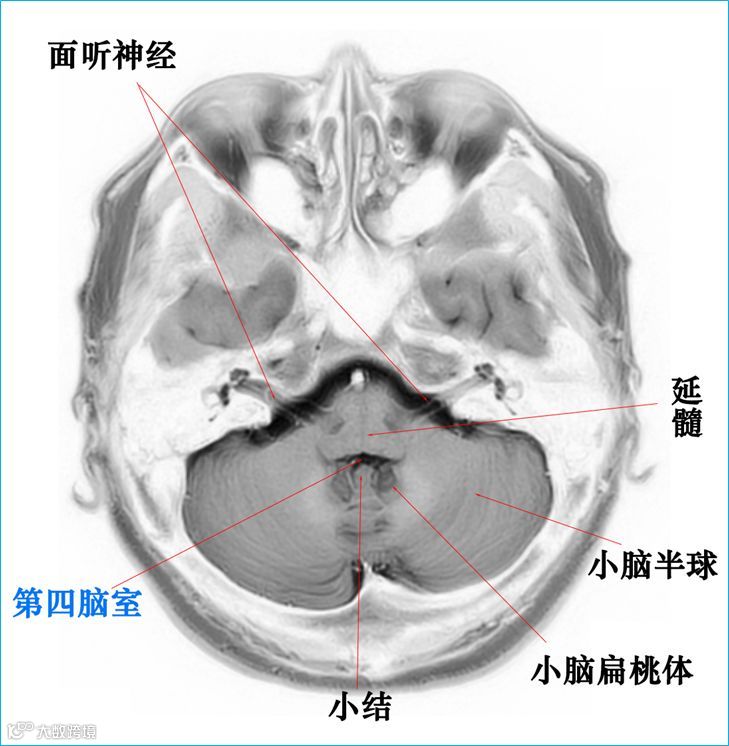

在T2WI反相图学下的颅脑断层解剖(吴晓安老师亲自手动标准)以及标本断层解剖,满满干货,坐在小板凳上,一起学习吧……